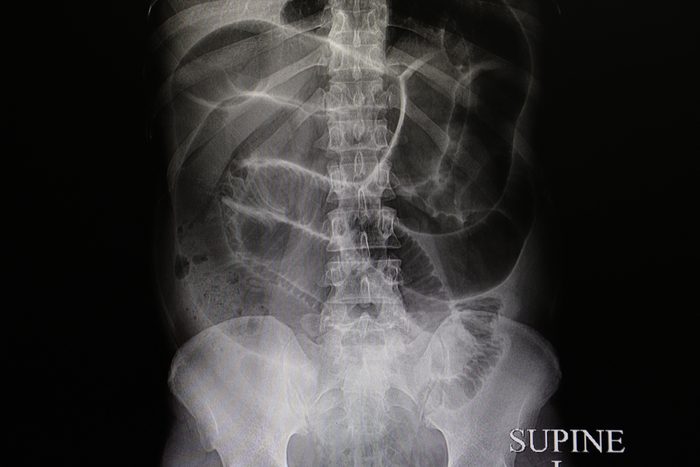

Constipation

Most of us can say we’ve experienced constipation at least a few times in our life, and it’s a common cause of lower abdominal pain. Constipation becomes increasingly common with age, as the bowels grow sluggish; certain conditions and some medications can make it worse. Constipation can also be a sign that you’re not eating enough fiber, not getting regular exercise, or failing to drink enough water, notes Dr. Salsberry. “Symptoms may include a sense of mid to lower abdominal fullness, a decrease in the number or frequency of bowel movements or straining to have a bowel movement—and, while the pain is generally not too severe, it is typically present for days to weeks in most cases,” he says. Luckily, you can manage most cases of constipation on your own by eating more produce, being more active, and drinking more water. You can also try stool softeners or mild laxatives such as Miralax. However, Dr. Salsberry recommends that you see a doctor if your symptoms come on suddenly, you have blood in the stools, or your home therapy doesn’t do the trick. “In these circumstances, it is important to exclude a bowel blockage from a tumor or growth in the intestines,” he says. Learn more about what causes constipation.